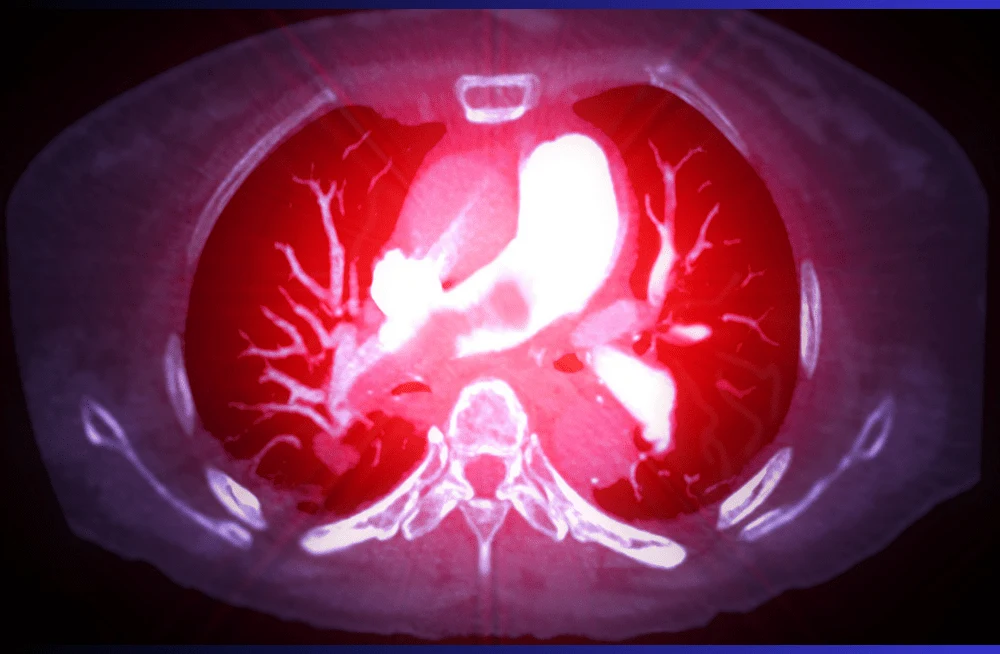

Spotting pulmonary embolism (PE) through computed tomography pulmonary angiography (CTPA) hinges on achieving sufficient contrast flow rates for clear visualization of pulmonary arteries. However, challenges arise when patients have difficult intravenous access, complicating the administration of high flow rates needed for optimal imaging.

In a recent study published in the Journal of Medical Imaging and Radiation Sciences, researchers investigated whether a low volume, low flow rate (LVLF) CTPA protocol could offer imaging quality comparable to that of a standard protocol. The study involved 151 patients who underwent CTPA using a 320-slice multi-detector CT scanner at a hospital in Singapore. Of these, 80 patients followed the standard protocol, receiving a fixed flow rate of 4.5ml/s and 50ml of contrast media. The remaining 71 patients underwent the LVLF protocol, which included reductions of up to 37% in flow rate and 30% in contrast volume administered.

Two independent radiographers evaluated the attenuation (measured in Hounsfield units, HU) of multiple pulmonary arteries across both protocols. They found no significant differences in HU measurements for any of the seven key regions of interest—including the main pulmonary trunk, right and left pulmonary arteries, and various lobar and subsegmental arteries—between the LVLF and standard protocols. Moreover, two independent radiologists assessed overall image quality using a standardized 5-point questionnaire and reported no significant variations between the LVLF and standard protocols.